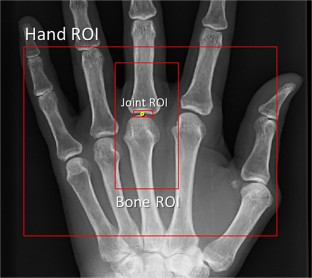

Fig. 1

Video clip to show the flow of pattern matching. After models of hand, bone and finger joint ROI specification are consecutively matched, the baseline and follow up images are been aligned on the target joint, then the JSDI is computed by considering the pixels within the joint ROI. (AVI 261 kb)